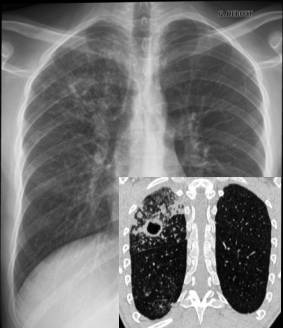

Dans la capitale de l'Ouest, la tuberculose pulmonaire (la forme la plus grave et qui peut être à l'origine du décès du malade) est la plus dominante. L'analyse de ces chiffres indique que malgré les différents programmes de lutte contre la tuberculose pilotés par les services de santé, et contrairement aux autres régions du pays, la wilaya d'Oran enregistre une augmentation dans le nombre de cas de tuberculose pulmonaire (contagieuse), ainsi que dans sa prévalence.

Ainsi, en 2010, près de 1.800 cas ont été enregistrés et autant en 2011. En 2009, quelque 1.950 cas de tuberculose (toutes formes confondues) ont été déclarés à Oran, dont 1.247 cas de tuberculose pulmonaire.

Au niveau de cette wilaya, l'incidence de l'affection de cette maladie est estimée à 85 cas pour 100.000 habitants. Or, au niveau national, 21.732 cas de tuberculose ont été déclarés dont 8.402 contagieux, soit une régression de la prévalence de 24,2 pour 100.000 habitants. La tuberculose pulmonaire mal traitée peut se transformer en tuberculose résistante.